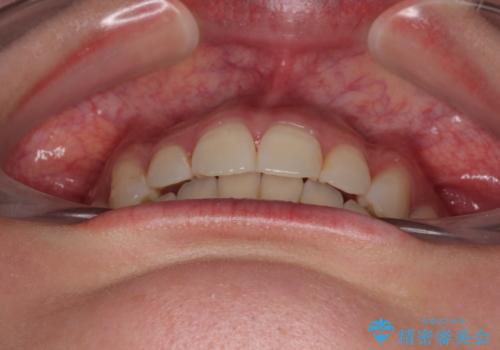

前歯の捻れを改善するとともに、口元が少しでも引っ込むように治療計画を立て、仕上げることができました。

長時間の装着を徹底し、遠方からの通院にもかかわらずしっかりと通院いただき、予想よりも早く治療を終えることができました。